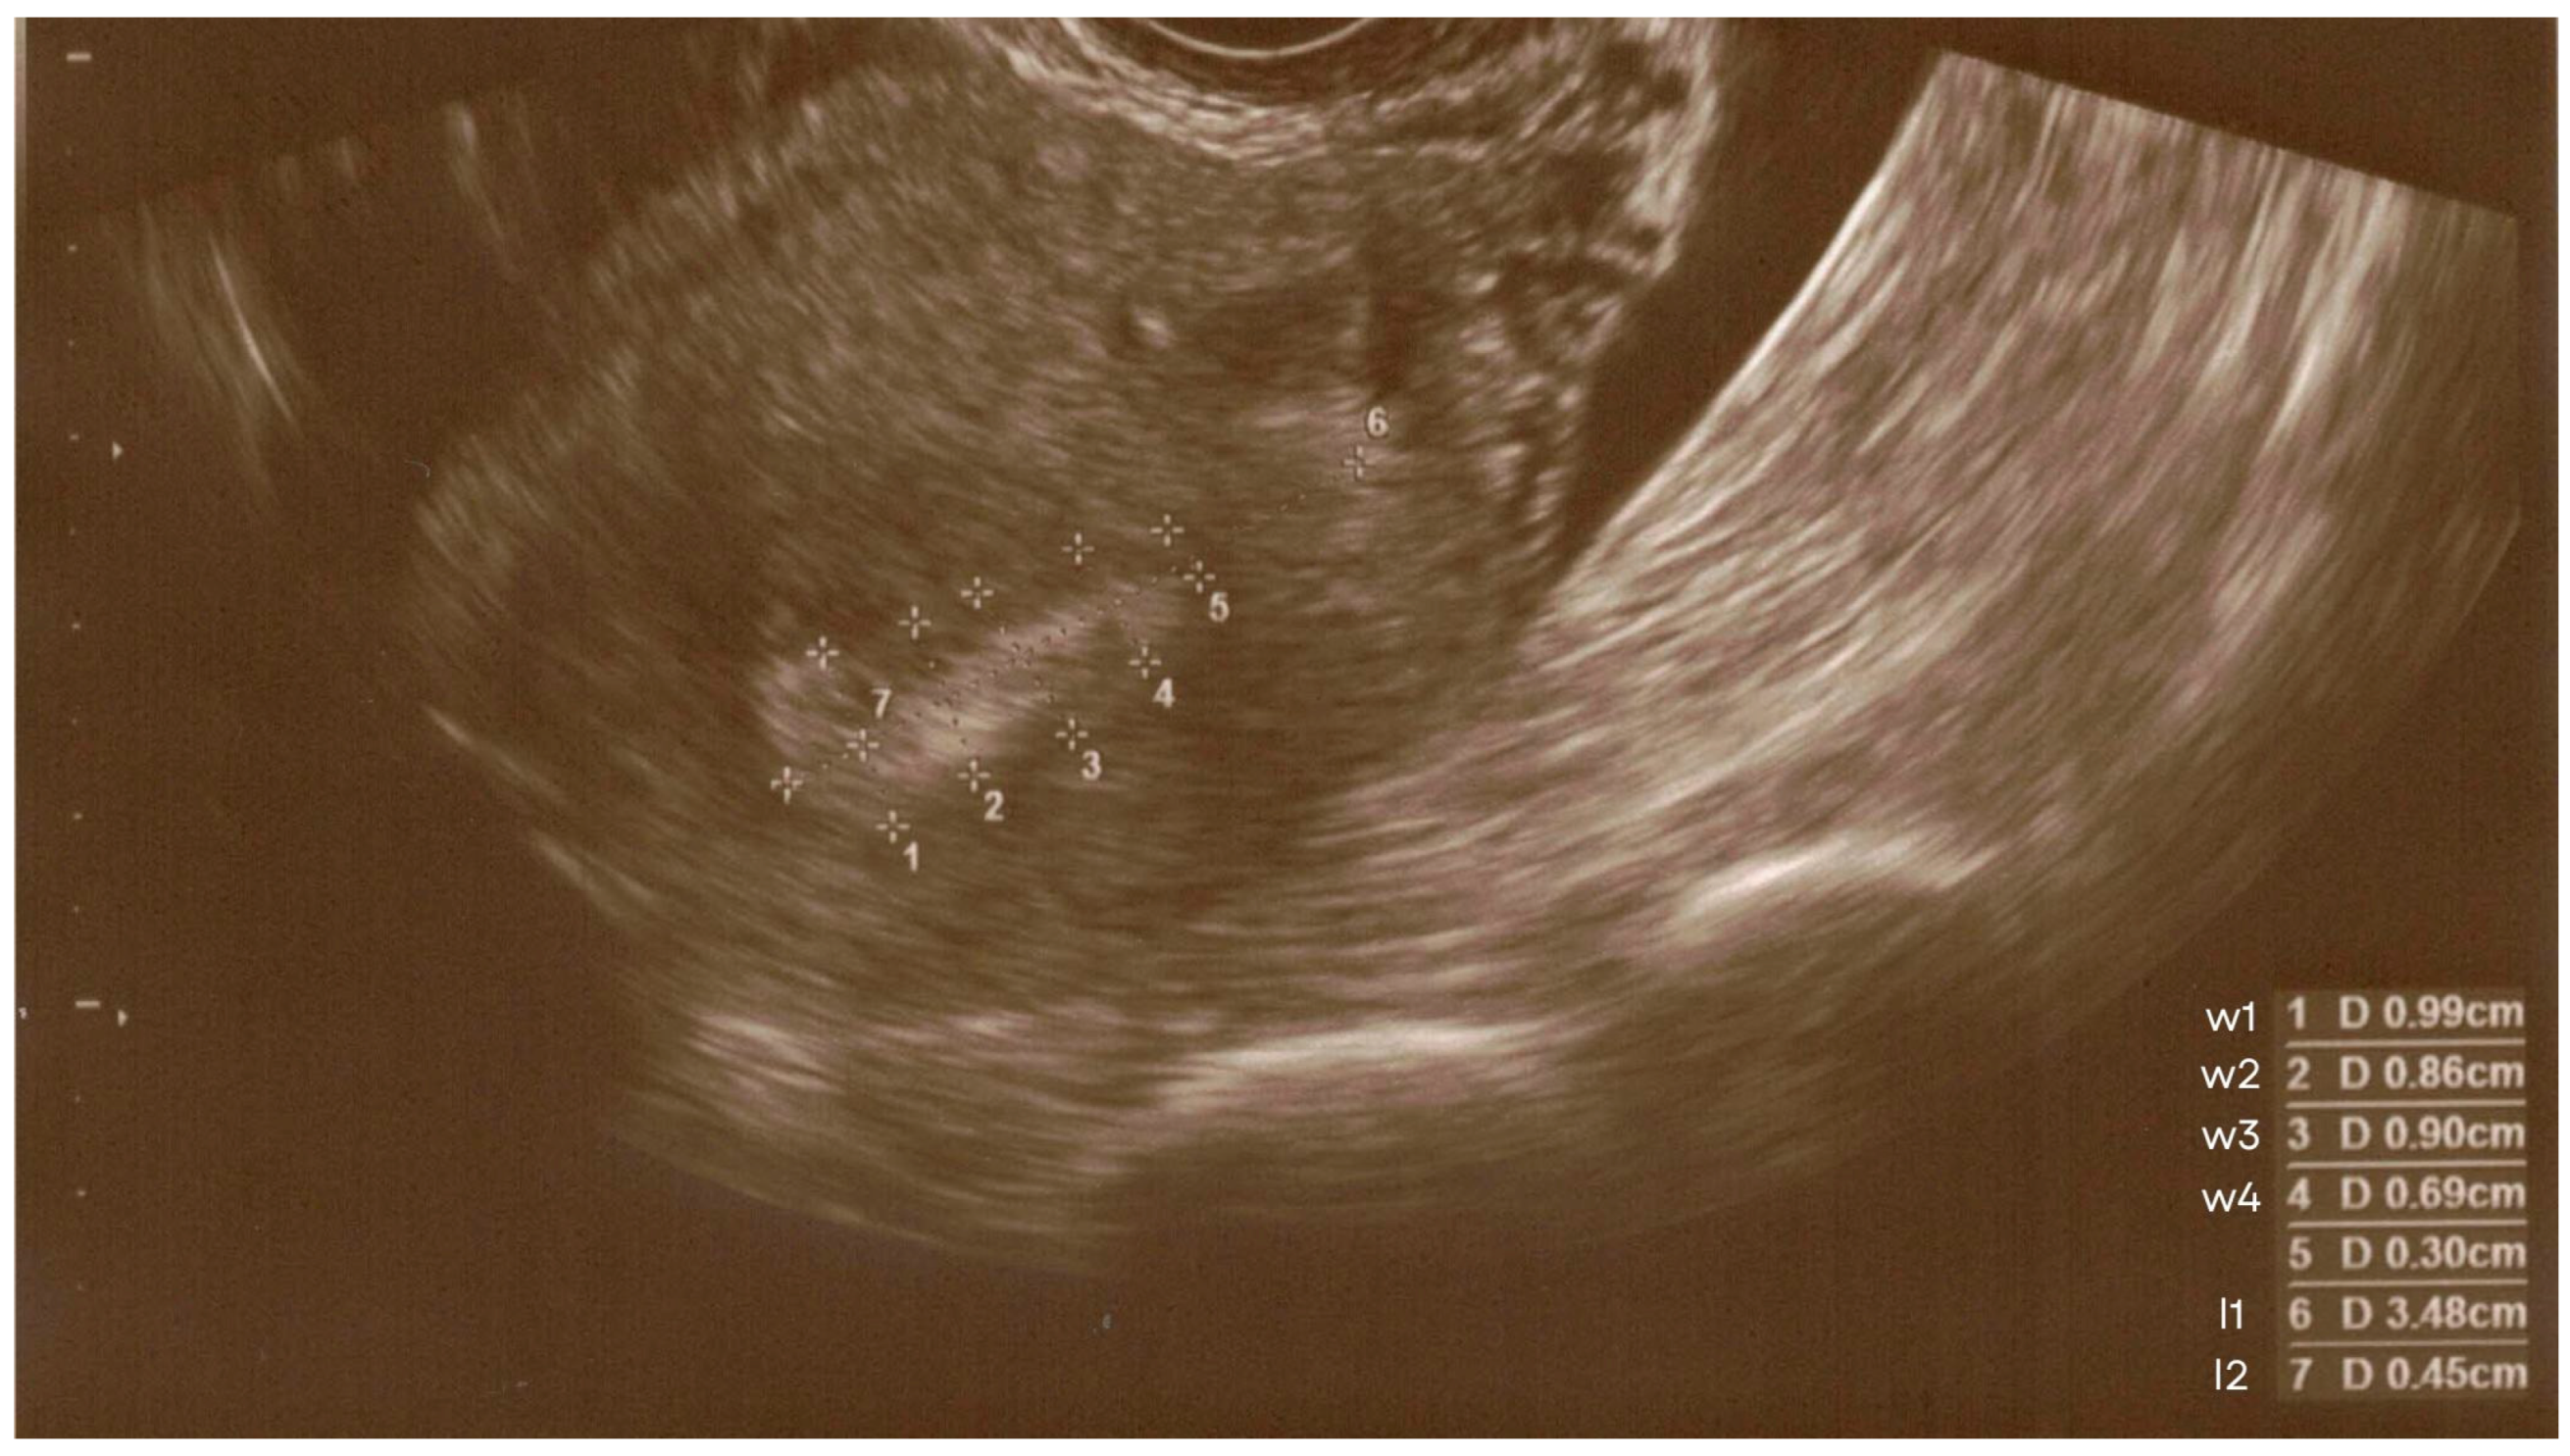

- l1—uterine length, measured between the highest point of the uterine fundus and the cervical opening;

- w1—width at the widest point of the endometrial outline;

- l2—distance measured along the junction defined during the l1 measurement, limited to the segment between the highest point of the uterine fundus and the intersection with the w1 measurement;

- w2, w3, w4—subsequent widths of the endometrial outline, measured along segments parallel to the w1 measurement and equidistant from each other by l2, continuing towards the cervical opening.